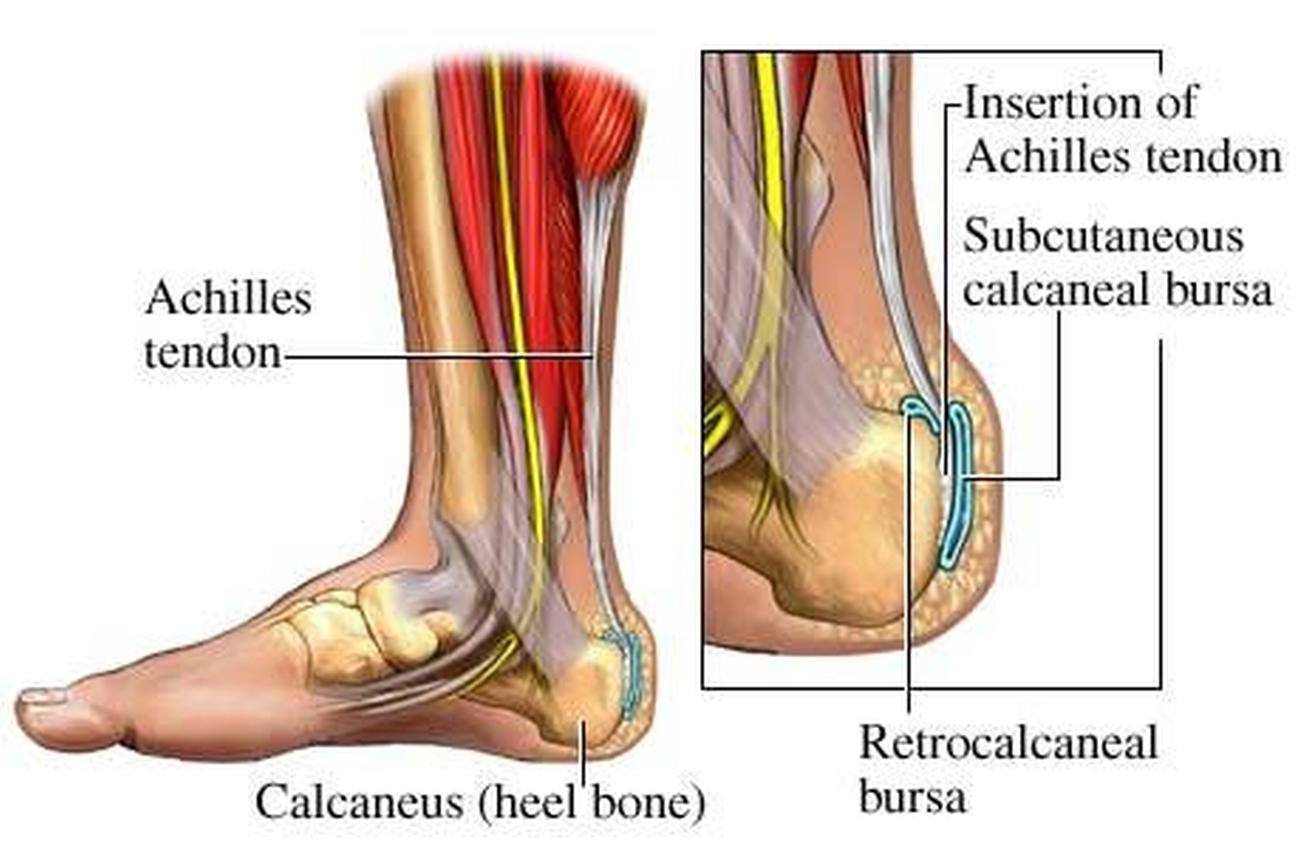

Анатомия голеностопа: Сухожилия и их строение